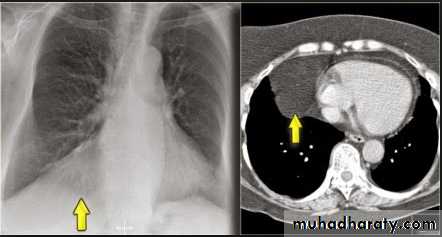

Unilateral rt. Hilar LNE, increase density, lobulated outline.

Identify main lower lobe pulmonary arteries: They can be compared to a little finger pointing downwards and medially. Sometimes, usually on the left side – it can appear only as the proximal phalanx of the finger.Interpretation: If the little finger shadow of the right lower lobe artery is not seen then you must check for evidence suggesting collapse of the right lower lobe.Identify the hilar point: Look for the site where the most superior upper lobe vessel – either vein or artery – crosses the lateral margin of the little finger. The point of crossing is known as hilar point and forms a horizontal “vee” (> or <).Interpretation: The left hilum must never be lower than the right hilum. Whenever a left hilum appears lower than the right hilum – look for other evidence suggestive of: 1- Collapse of either the left lower lobe or of the right upper lobe or 2- Enlargement of the right hilumBilateral hilar LNE